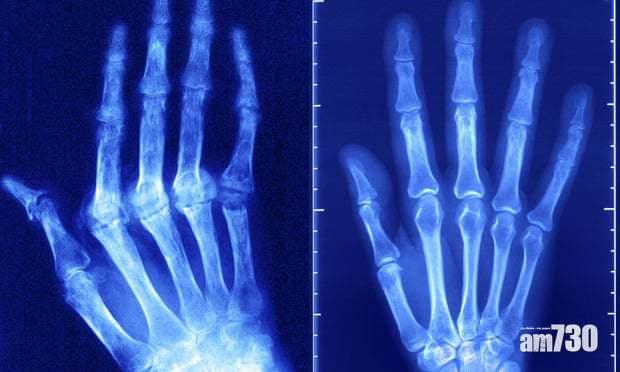

然而,天氣轉凍只是一個觸發點,將深層的關節磨損及發炎問題顯露無遺。而導致以上問題的成因,很可能是關節軟骨已失去原有的功效。軟骨覆蓋於不同骨骼交接的表面,為身體的天然避震系統,是身體的「易耗品」。在日積月累的勞損、不當受力及營養流失下,軟骨就會逐漸變薄、失去彈性,甚至表面變得粗糙,令骨骼承受的壓力增加,造成嚴重磨損及發炎問題,輕輕一動亦會引起強烈疼痛。